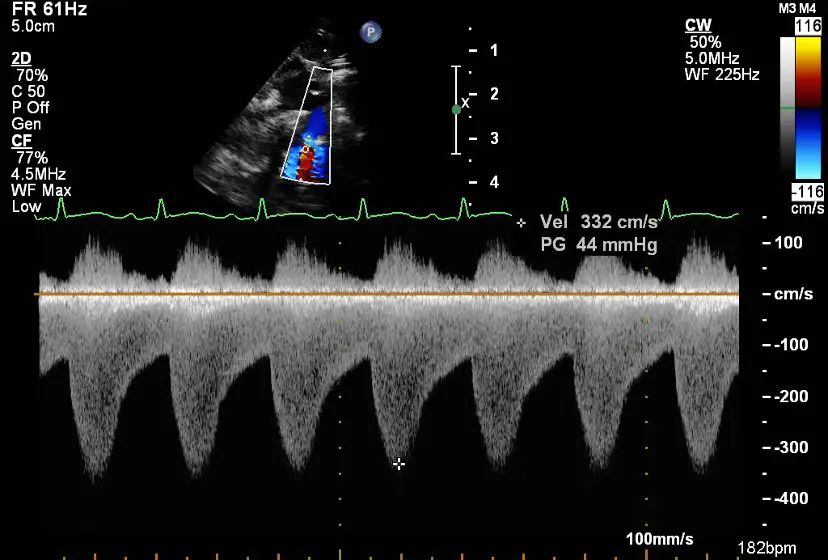

- Continuous-wave Doppler enables assessment of transaortic gradients and abdominal aortic flow.

- Suprasternal Doppler for Coarctation of the Aorta

- The Doppler doesn’t go back to baseline, i.e. doesn’t get back to